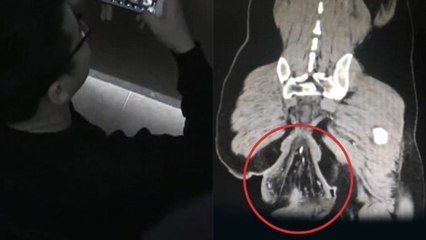

Cet homme se fait opérer après avoir avalé 40 couteaux !